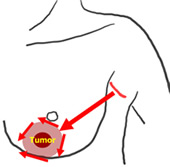

従来の乳腺内視鏡手術は、皮膚直下を剥離することにより手術操作を行っていましたが、剥離範囲が広くなると知覚神経の損傷もひどくなります。この方法は、全て腋窩の傷のみから操作し、乳腺の背側から腫瘍部分の乳腺を切除してきますので、神経損傷や皮膚障害が起こりません。また、乳房のどの位置に腫瘍があっても手術可能です。乳輪縁切開では乳頭・乳輪の変形を起こす可能性がありましたが、その心配もいりません。

腋窩に2.5 cmの皮膚切開(腫瘍の位置によって乳輪縁にも2.5cm)を施し、5 mmのビデオスコープを使い、モニターで見ながら、手術操作を行います。癌病巣を周囲1~2 cmの乳腺組織とともに切除します。さらに、腋窩リンパ節郭清を行います。乳腺の欠損部分は周囲の脂肪組織を寄せたり、側胸部脂肪織や人工合成繊維網を充填して、形を整えます。腋窩リンパ節郭清を行う場合には腋窩のリンパ液漏出に対して、J-VACドレーンを留置します。皮膚は、吸収糸で皮下縫合し、表面はダーマボンドという接着剤で固定します。これにより、傷を完全に密閉出来ますので、水に濡らしても平気ですし、傷の消毒・抜糸は要りません。傷は、腋の下に隠れる目立たないところに、わずか2~3cmの小ささで、しかも綺麗に出来上がりますので、皆さんが満足されています。